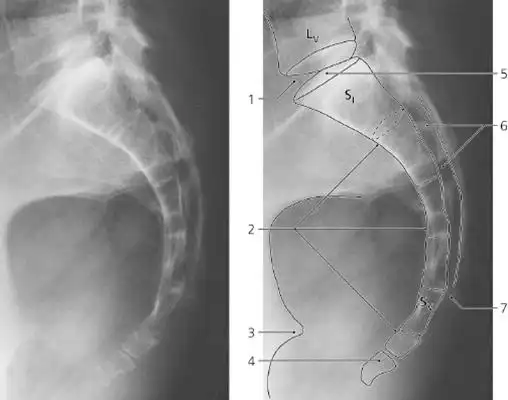

骶尾椎影像报告怎么写? - 知乎

【读片】骶尾椎ct [病例帖]

x13837尾骨侧位片